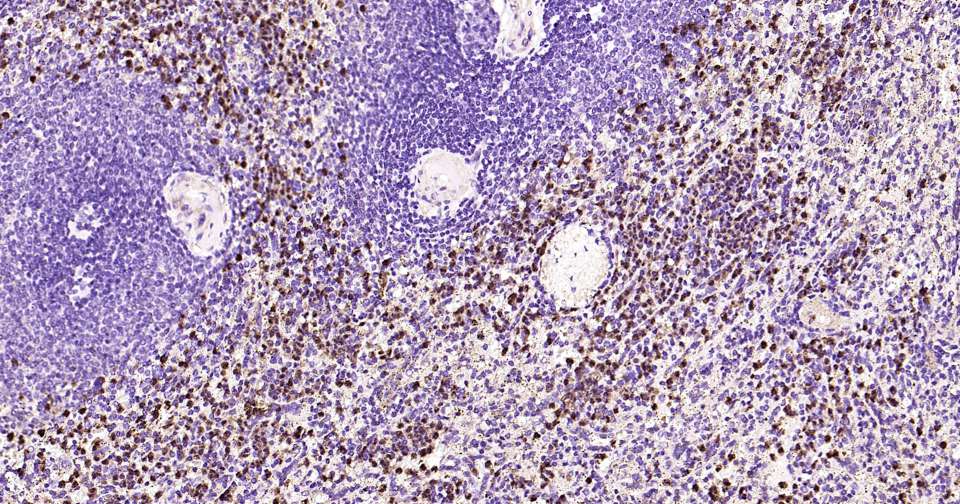

Immunohistochemical analysis of paraffin embedded mouse spleen tissue slide using IHC0404 (JNK1/3 IHC Kit).

Immunohistochemical analysis of paraffin embedded human spleen tissue slide using IHC0404 (JNK1/3 IHC Kit).

Immunohistochemical analysis of paraffin embedded rat spleen tissue slide using IHC0404 (JNK1/3 IHC Kit).